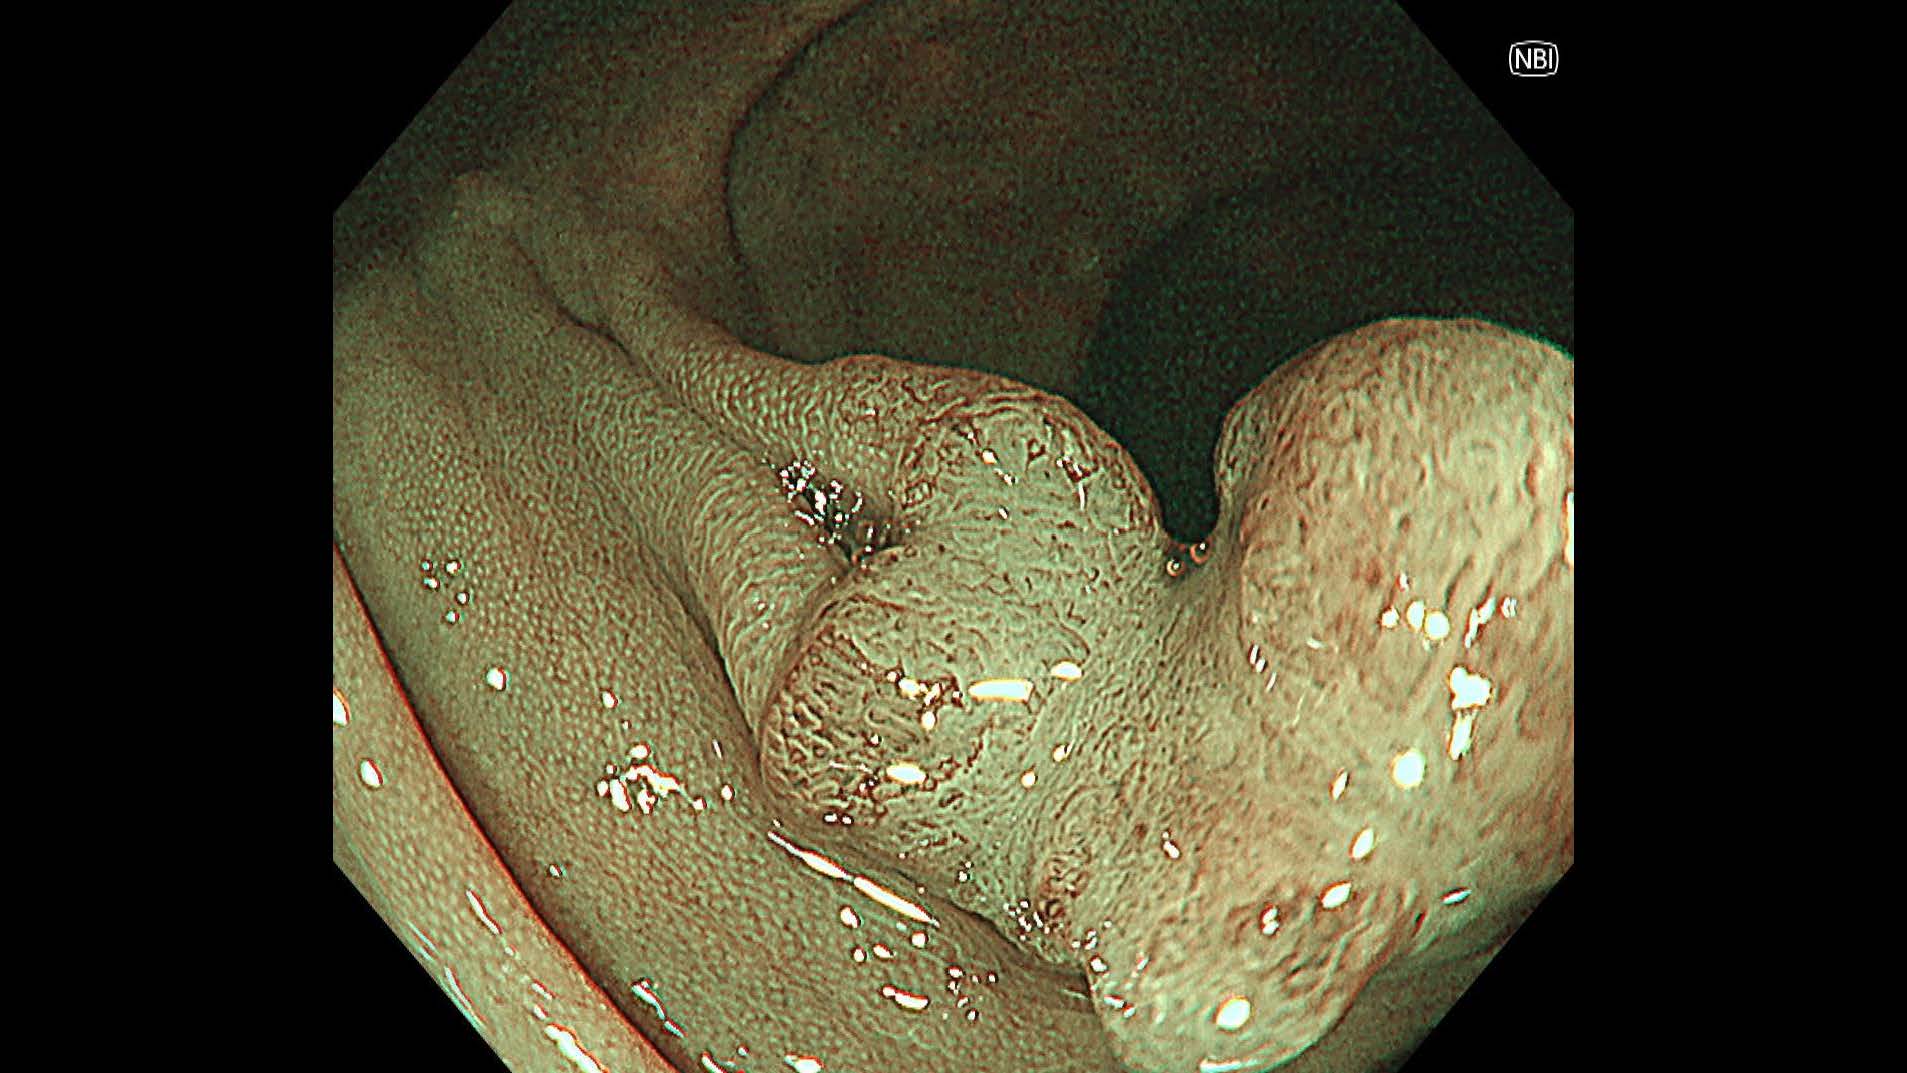

消化管Mapping~大腸~ 2025.6.11

消化管Mapping